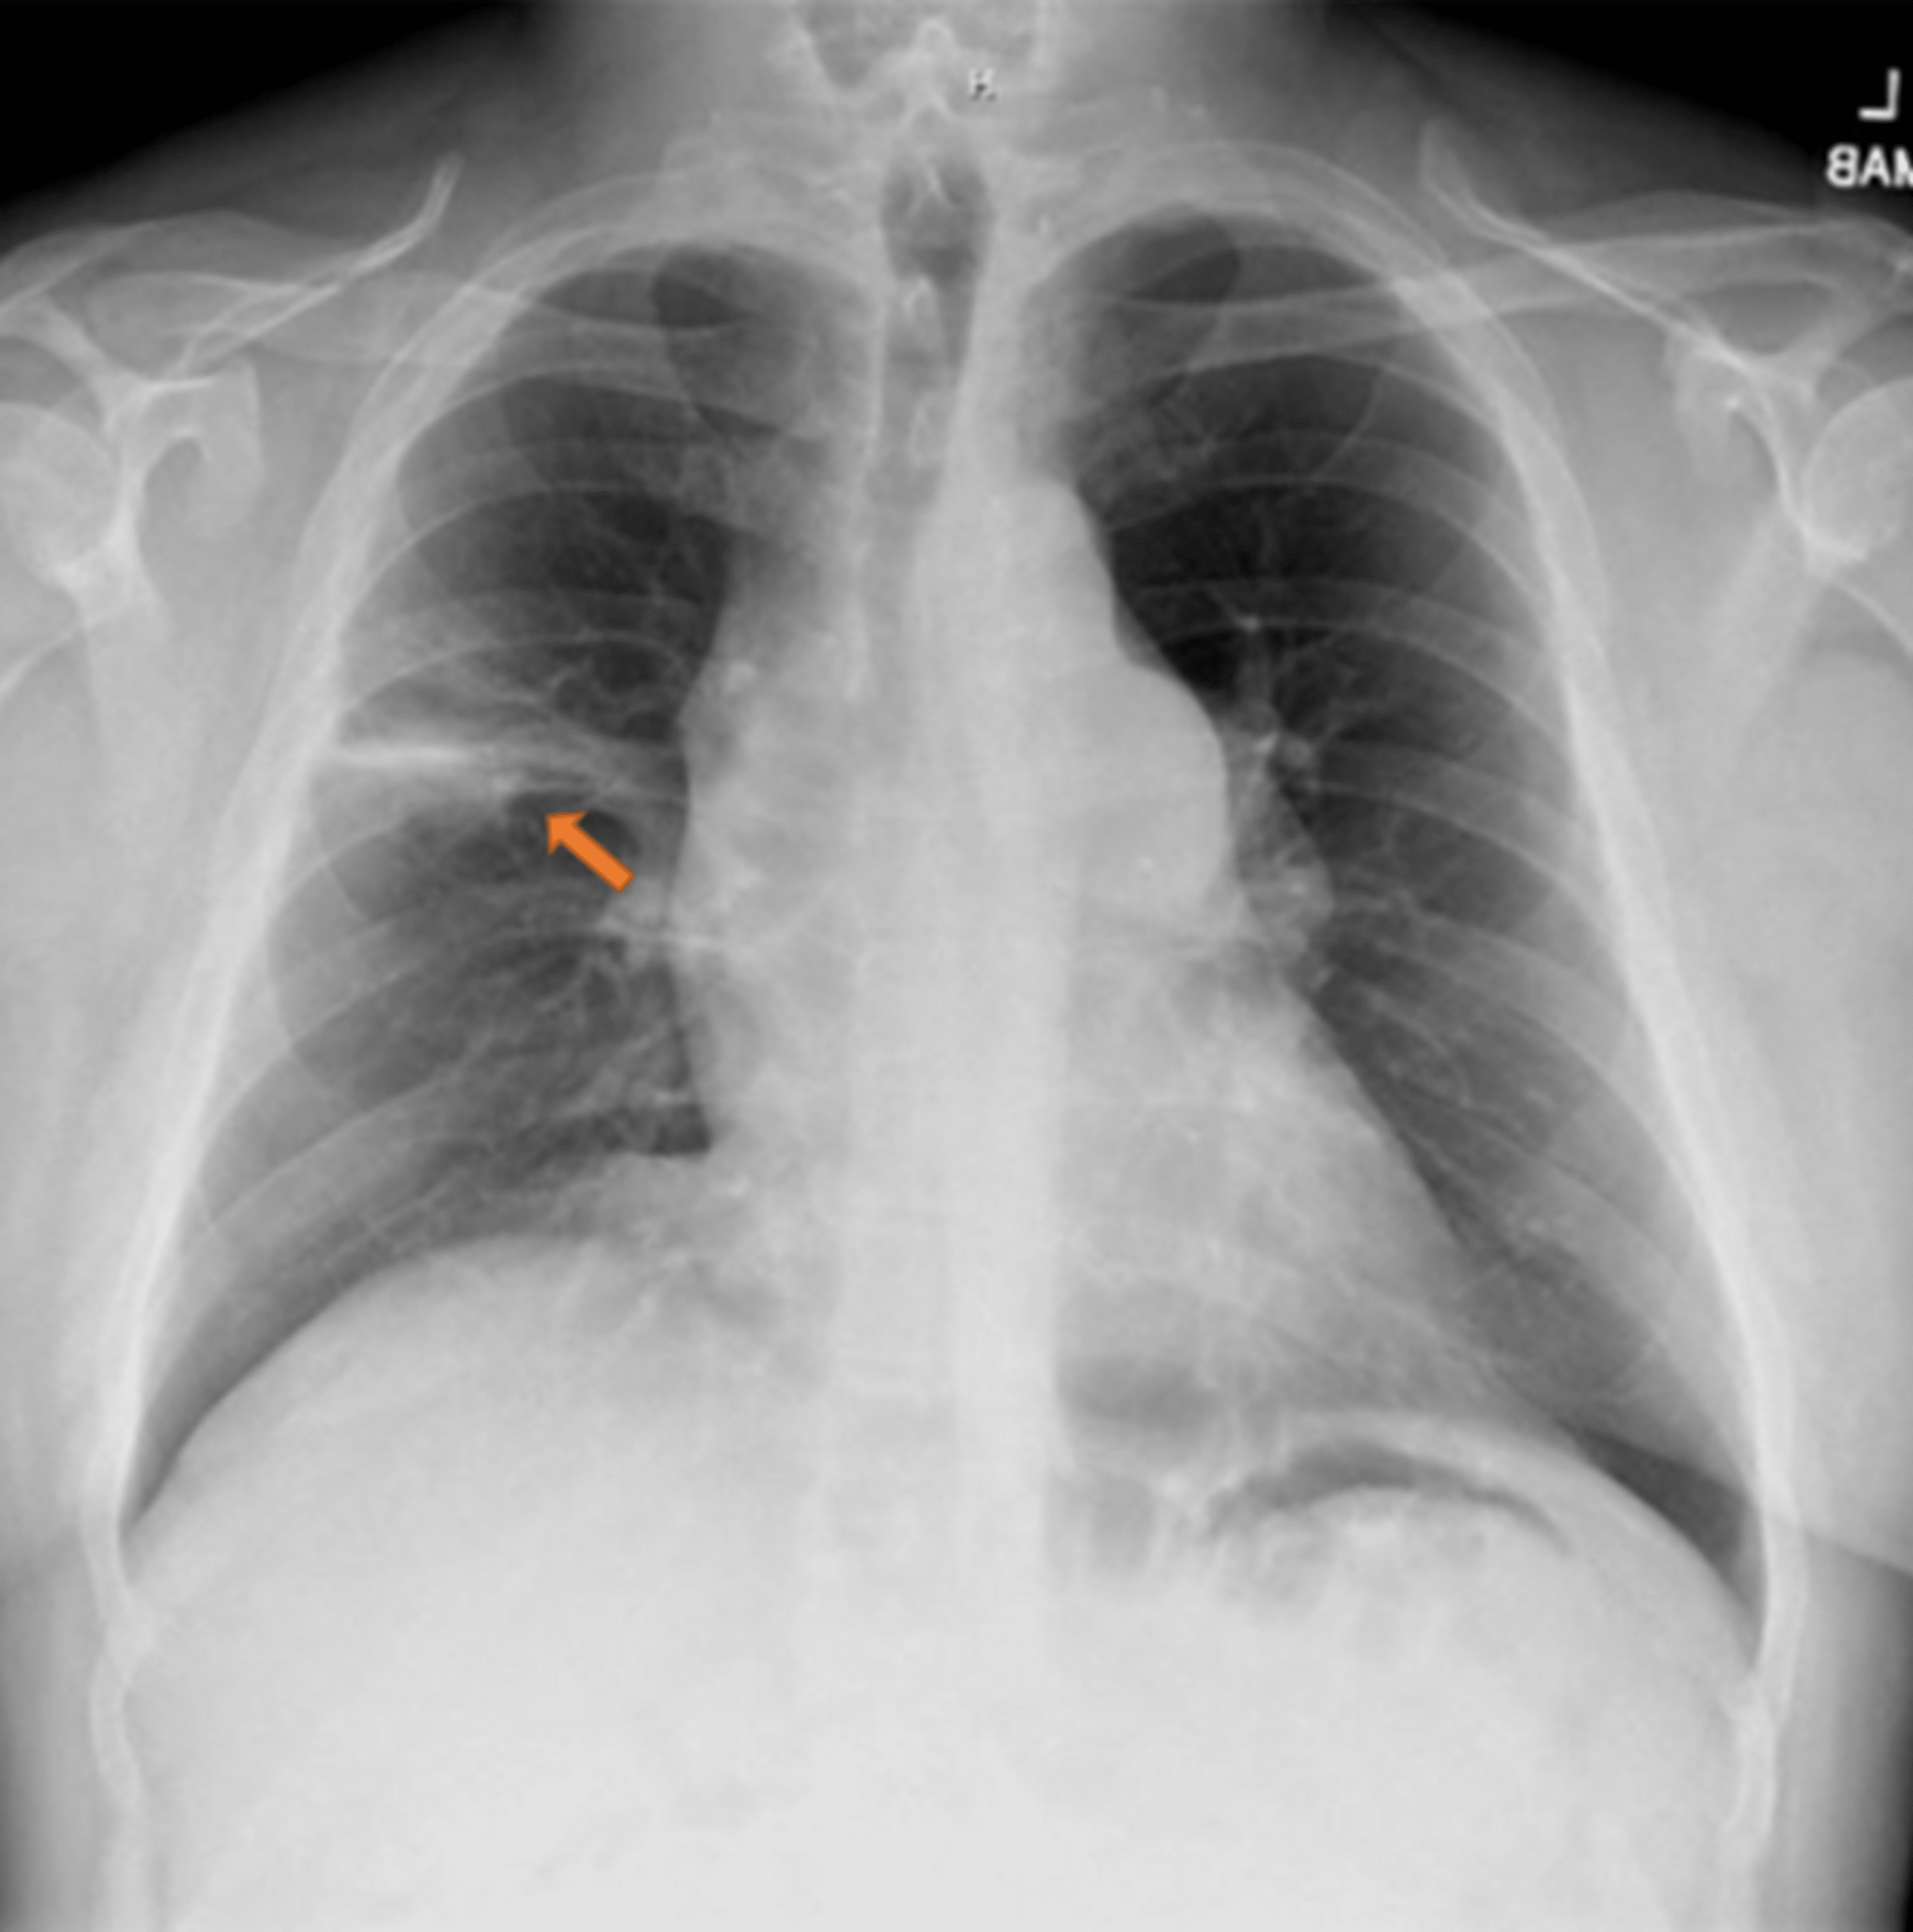

Chest Xray documented right lower pneumonia. Download Scientific Diagram Repeat Chest X Ray For Pneumonia — we aim to assess whether radiation exposure from repeat cxrs (0.02 msv) and ct thorax imaging (7.0 msv) is justified, and how many. in patients who have clinically improved, follow up cxr is presumably intended to rule out malignant neoplasms that have. — the diagnosis of cap generally requires the demonstration of an opacity on chest. Repeat Chest X Ray For Pneumonia.